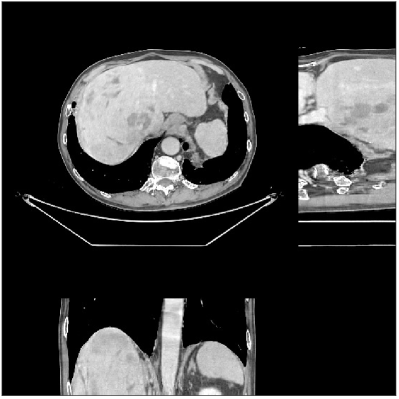

Fig.Β 5 shows the reconstructions and the corresponding error (magnitudes) images (shown for the central axial, sagittal, and coronal planes) for FDK, PWLS-EP, and PWLS-ULTRA () with the patch-based weights. Compared to FDK and PWLS-EP, PWLS-ULTRA significantly improves image quality by reducing noise and preserving structural details (see zoom-ins). Fig.Β 6 shows the RMSE for each axial slice in the PWLS-EP and PWLS-ULTRA (with the weights ) reconstructions. PWLS-ULTRA clearly provides large improvements in RMSE for many slices, with greater improvements near the central slice.

Fig.Β 10 shows the reconstructions (shown for the central axial, sagittal, and coronal planes in the 3D volume) for PWLS-EP and PWLS-ULTRA with patch-based weights () from low-dose abdomen scans. For the sagittal and coronal planes, we show the central out of axial slices. The supplement provides PWLS-EP reconstructions with different regularization strengths. The PWLS-ULTRA reconstructions in Fig.Β 10 have reduced noise as well as higher resolution, better structural details and shaper image edges than the PWLS-EP results. These results are further example of the potential performance of the proposed PWLS-ULTRA method in clinical settings.